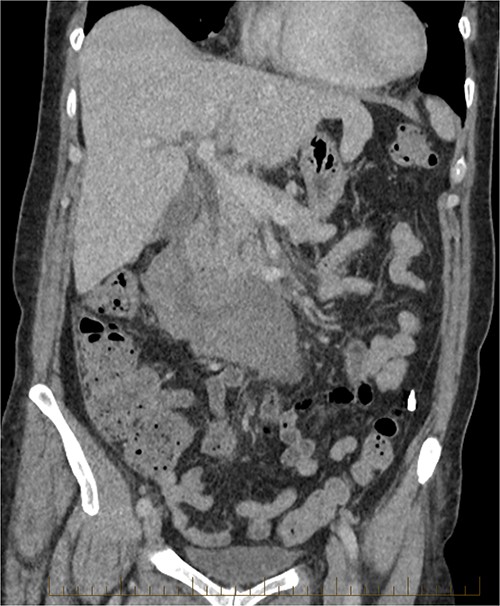

The radiologist suggested a computer tomography (CT) scan to further explore the potential causes for this fluid. The CT abdomen and pelvis revealed extensive oedema and induration surrounding the duodenum with a complex hyperdense fluid, extending from this site to the paracolic gutters and into the pelvis. While these findings are suspicious of a paraduodenal hemorrhage from a ruptured duodenal ulcer and hemoperitoneum, they were not typical for perforated duodenal ulcer or erosion into the blood vessels. Differentials were an infiltrating mass either fibrotic or of a lymphoproliferative origin. However, this could not explain the complex fluid in the abdomen (Figs 1 and 2).

CT abdomen, coronal view. Hyperdense fluid centered around the duodenum and tracking into the paracolic gutters. Appearance concerning for paraduodenal hemorrhage, infiltrating mass was considered less likely.